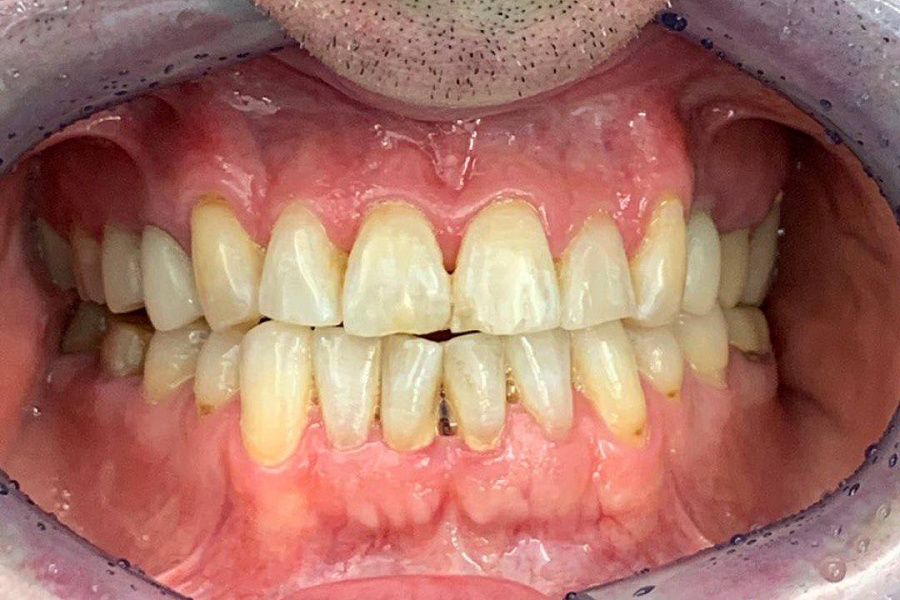

Наш постоянный клиент, который настаивал только на лечении кариеса. Несмотря на ряд проблем: стираемость зубов, перекрестный прикус, который и вызывал увеличение стираемости, пациент не хотел делать комплексную работу.

В итоге из-за неправильного прикуса стираемость зубов прогрессировала и нам удалось убедить пациента заняться данной проблемой серьезно.